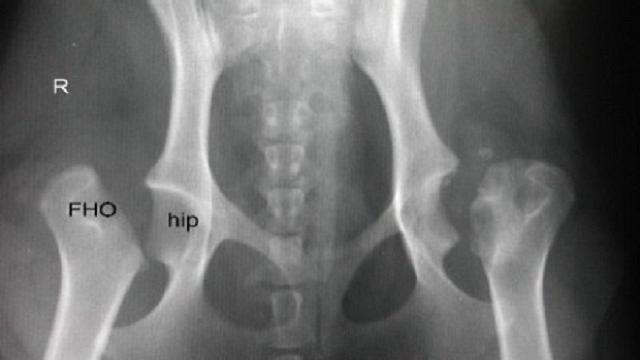

Al examen radiológico de la articulación coxofemoral, la evidencia de una pérdida de la densidad radiográfica de la cabeza y cuello del fémur, con aplanamiento de la cabeza femoral, que deriva en una incongruencia entre las superficies articulares, permiten confirmar el diagnóstico clínico.

El tratamiento de esta enfermedad osteo-articular degenerativa debe ser quirúrgico; la escisión de la cabeza y cuello del fémur con o sin la colocación de prótesis de cadera han dado excelentes resultados, aliviando por completo el dolor de la mascota. Si bien, tras la escisión sin prótesis permanece cierto grado de claudicación tras la resolución quirúrgica, esta se debe al acortamiento del miembro afectado por efecto de la cirugía.